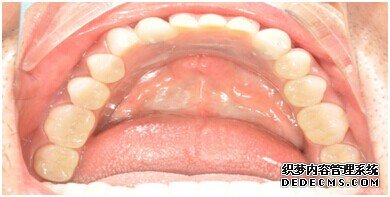

种植设备检查牙齿

成功植入种植体后的效果图